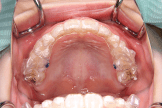

小学生からのマウスピース型カスタムメイド矯正歯科装置(製品名インビザライン 完成物薬機法対象外)は小学生のために開発された新しいマウスピース装置です。大人に比べると、まだ高さの低いお子さんの歯にもぴったりとフィットするように開発されました。また、アタッチメントと呼ばれるマウスピース型カスタムメイド矯正歯科装置(製品名インビザライン 完成物薬機法対象外)による矯正治療に必要不可欠な補助装置も子ども専用に開発されました。小学生からのマウスピース型カスタムメイド矯正歯科装置(製品名インビザライン 完成物薬機法対象外)は、小学生でも取り扱いやすくストレスなくお使いいただけるような特別な製品となっております。